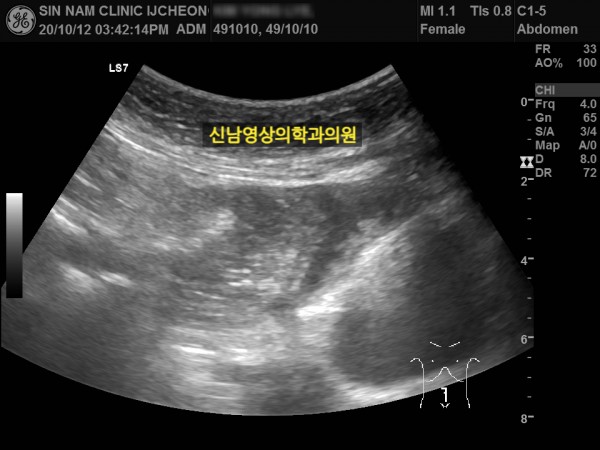

본 환자분께서는 사흘 정도 지속되는 복통과 고열로 내원하신 60대 중반의 환자분입니다.

복통 부위의 병변을 확인하기 위해서 복부 촬영과 복부 초음파검사를 진행했고, 맹장은 이상이 없고, 대장 주위로 복강삼출액(물)이 둘러싸고 있으면서 상행대장부위의 부종이 심하게 발견되었습니다.

원내 피검사상 백혈구 수치가 높아 대학병원 응급실로 전원 조치하고 응급수술을 받으셨고...

1년 뒤 수술 부위에 탈장이 발생하셔서 탈장 수술을 받으셨던 분입니다.